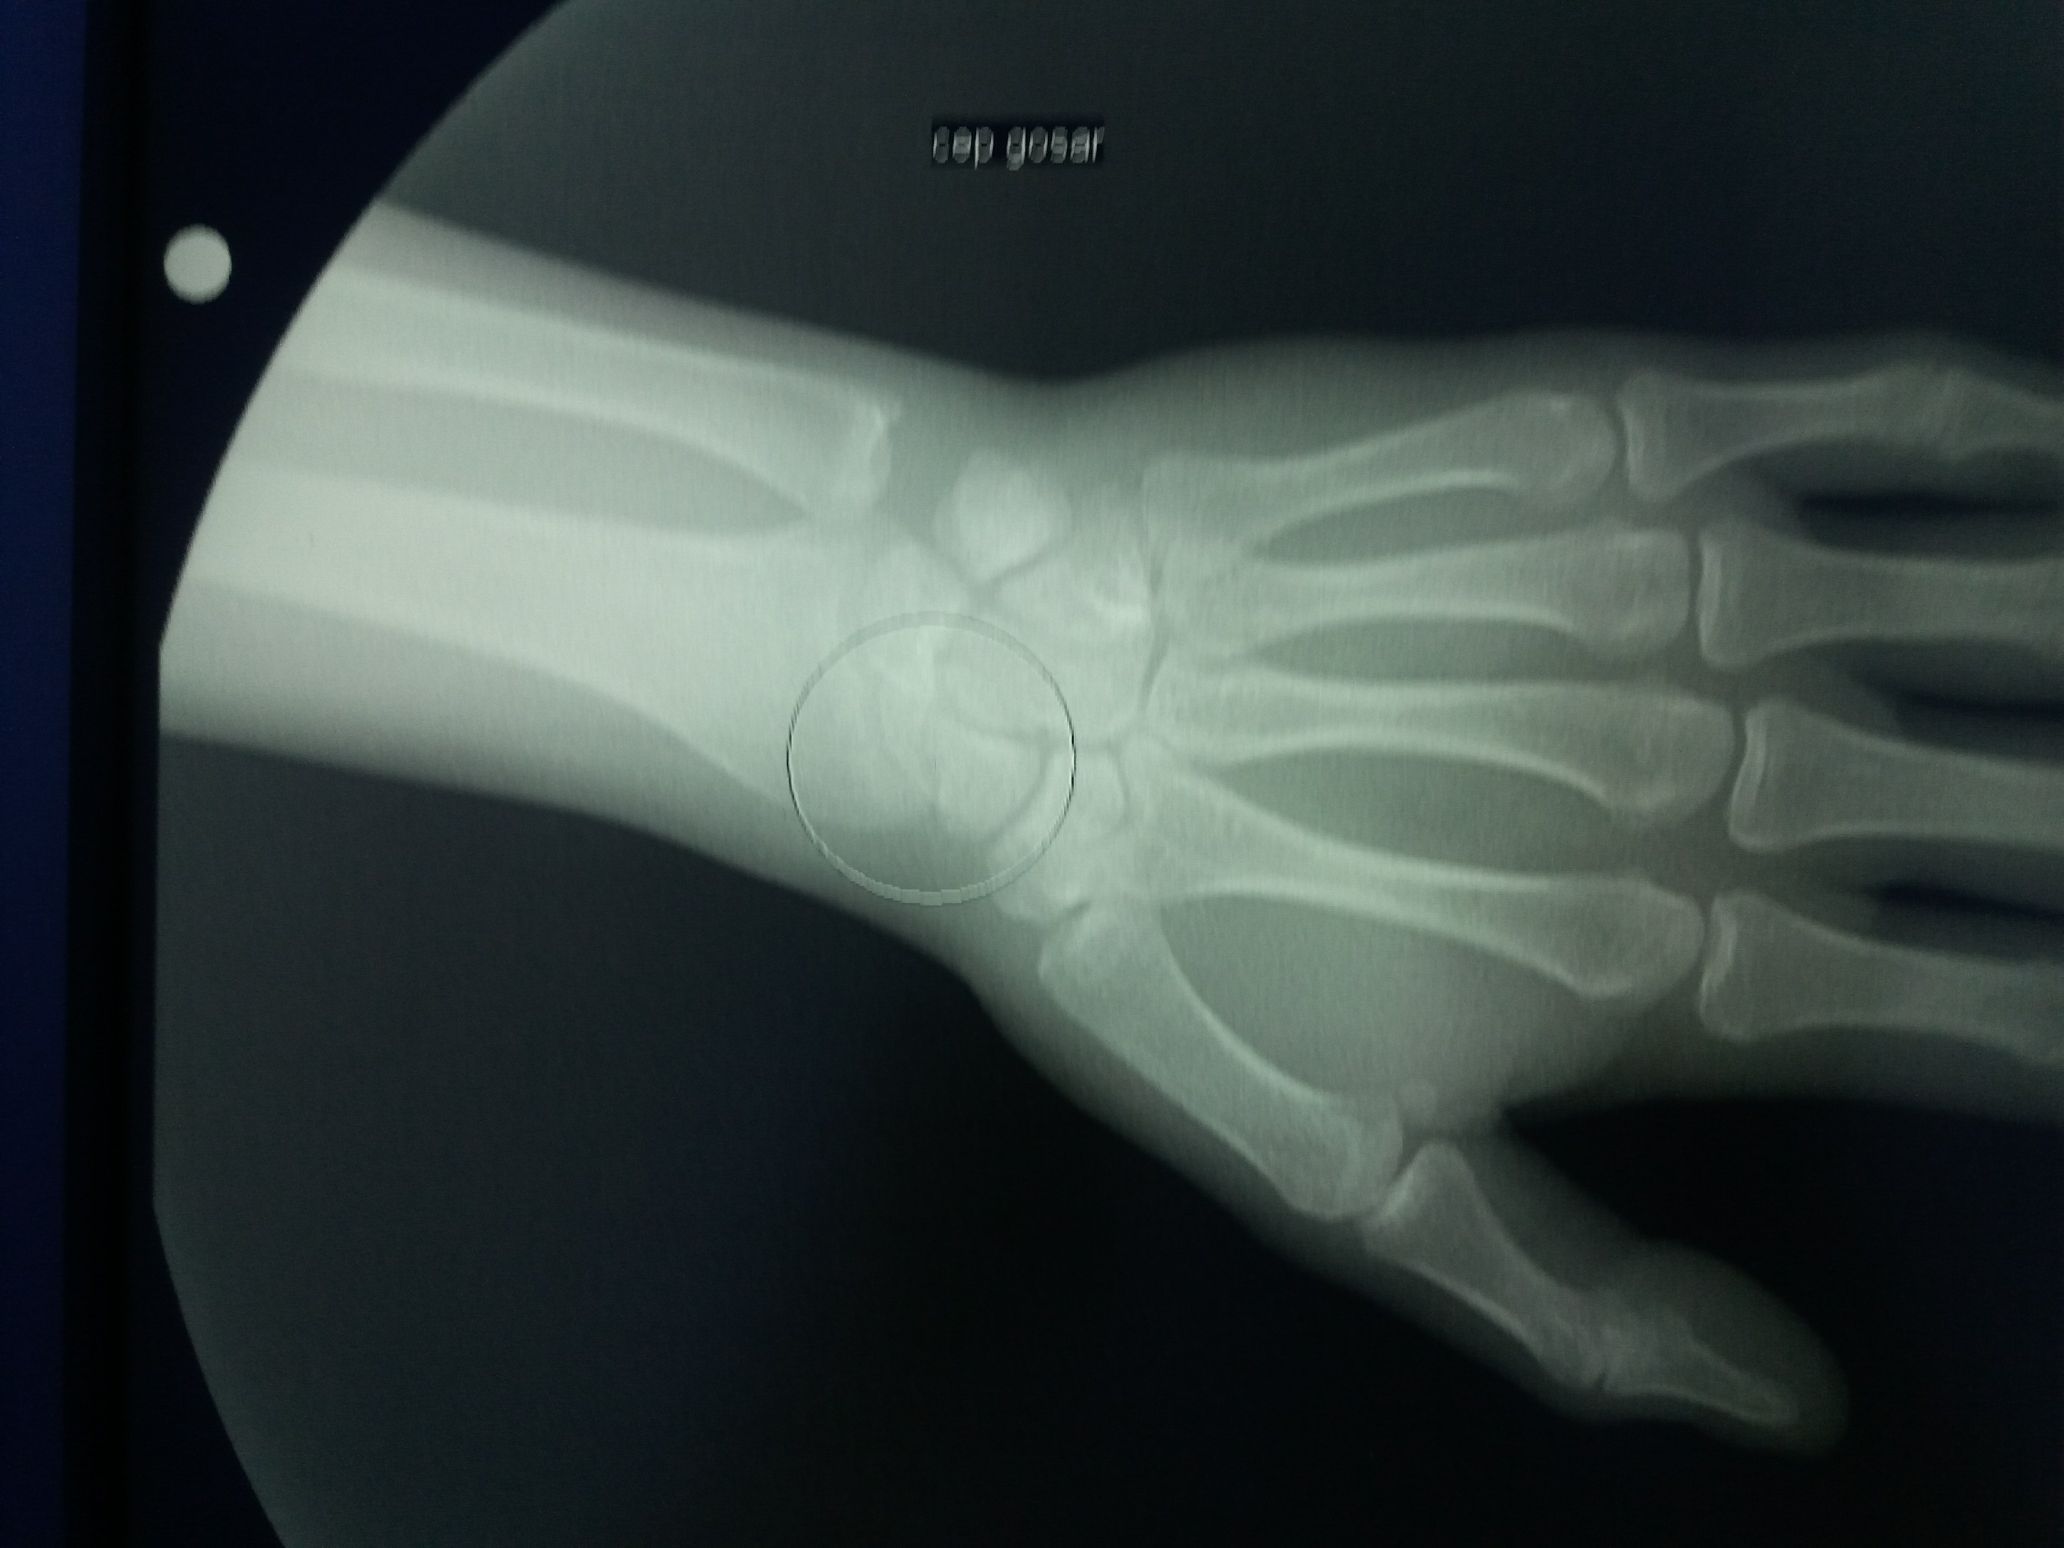

What do you see.tell me please

Trauma

Arm

Fall